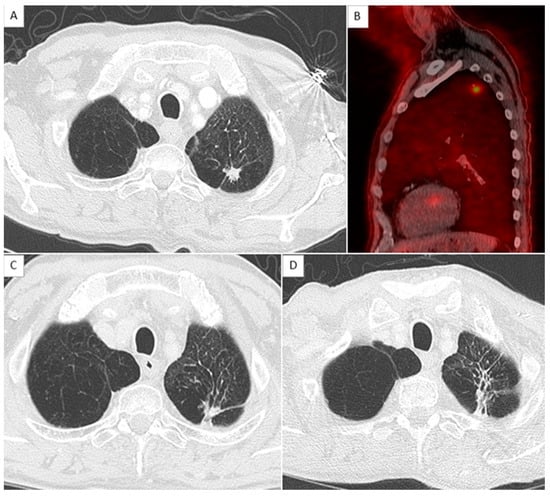

2.4. CT Scan Monitoring

2.5. Local Relapse Definition

- Kato, S.; Nambu, A.; Onishi, H.; Saito, A.; Kuriyama, K.; Komiyama, T.; Marino, K.; Araki, T. Computed tomography appearances of local recurrence after stereotactic body radiation therapy for stage I non-small-cell lung carcinoma. Jpn. J. Radiol. 2010, 28, 259–265. [Google Scholar] [CrossRef]

- Huang, K.; Dahele, M.; Senan, S.; Guckenberger, M.; Rodrigues, G.B.; Ward, A.; Boldt, R.G.; Palma, D.A. Radiographic changes after lung stereotactic ablative radiotherapy (SABR)—Can we distinguish recurrence from fibrosis? A systematic review of the literature. Radiother. Oncol. J. Eur. Soc. Ther. Radiol. Oncol. 2012, 102, 335–342. [Google Scholar] [CrossRef] [PubMed]

- Huang, K.; Senthi, S.; Palma, D.A.; Spoelstra, F.O.; Warner, A.; Slotman, B.J.; Senan, S. High-risk CT features for detection of local recurrence after stereotactic ablative radiotherapy for lung cancer. Radiother. Oncol. J. Eur. Soc. Ther. Radiol. Oncol. 2013, 109, 51–57. [Google Scholar] [CrossRef] [PubMed]

| Sequentially enlarging mass-like lesion | 12.0 | 1.2–120.1 | 0.034 | Yes | 1 |

| Craniocaudal growth | 19.2 | 1.8–199.9 | 0.013 | Yes | 1 |

| Bulging margin | 10.6 | 1.5–76.1 | 0.019 | Yes | 1 |